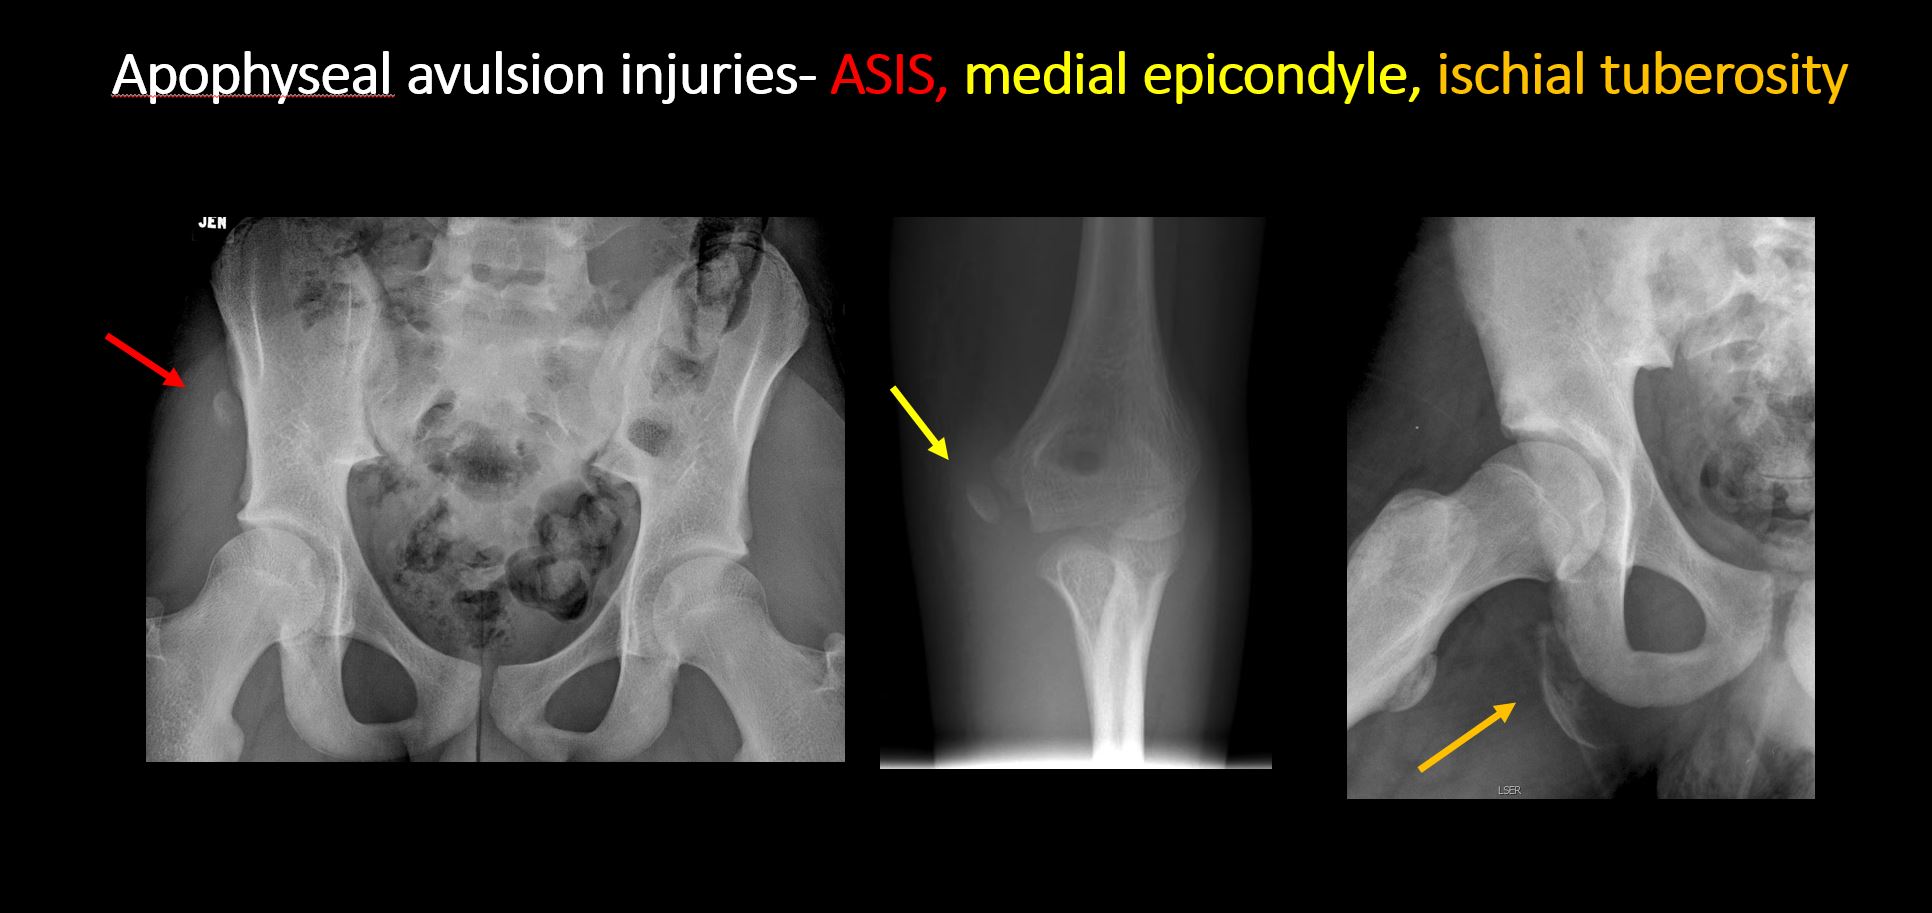

The apophysis, epicondyle, secondary ossification center, or accessory ossicle is displaced or otherwise abnormal (e.g. avulsed ASIS, medial epicondyle of the humerus, etc). |

No | NA |